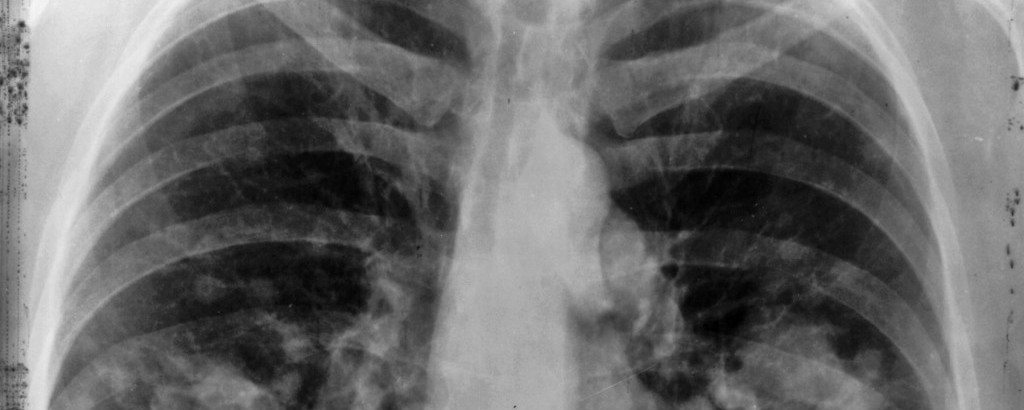

Önceden geçirilmiş akciğer hastalıkları akciğer kanseri riskini arttırıyor

akciğer-kanseri-25 bin’den fazla bireyi kapsayan yedi araştırmanın toplu analizi sonucunda, akciğer kanseri gelişimi riski ve birtakım basit solunumsal hastalıklar arasında bazı bağlantılar bulundu.